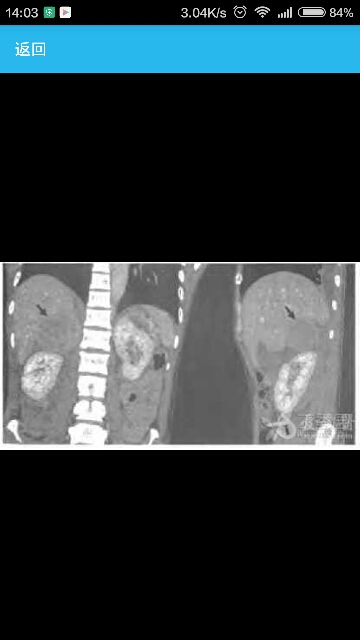

腹部增强CT示右侧肾上腺区可见一类圆形混杂密度影,边界清晰,呈渐进性轻度强化,大小约68 mm×61 mm×60 mm。